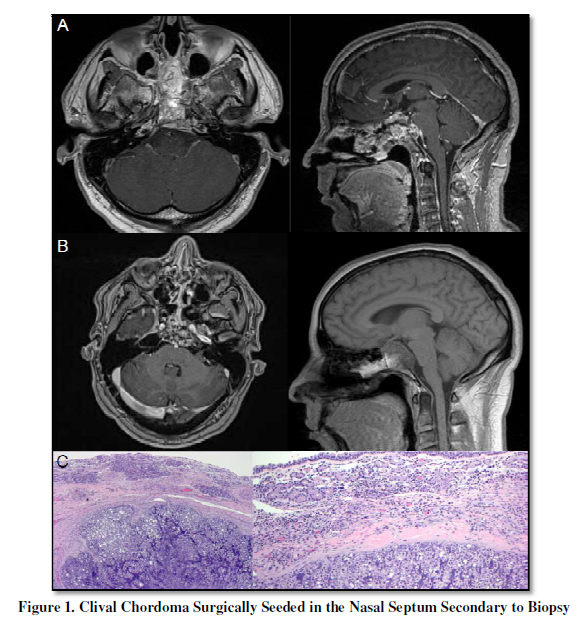

Pre-operative axial and sagittal T1-weighted MRI of

the brain with contrast showed a heterogeneously enhancing mass that appeared

to originate from the superior half of clivus, with rostral and dorsal invasion

of the sellar region and cavernous sinus bilaterally (Figure 1A). The brainstem

was compressed at the level of the pons caudally, and the optic chiasm and

pituitary infundibulum were displaced upward.

The lesion extended rostrally along the nasal septum, occluding parts of

the nasal cavity.

MRI findings were

suggestive of chordoma, Therefore, the patient underwent an image-guided

Post-procedural axial

T1-weighted MRI with gadolinium, and sagittal T1-weighted MRI without

gadolinium confirmed generous debulking of the tumor (Figure 1B). The pathology of the nasal septal mass was

consistent with chordoma (Figure 1C).